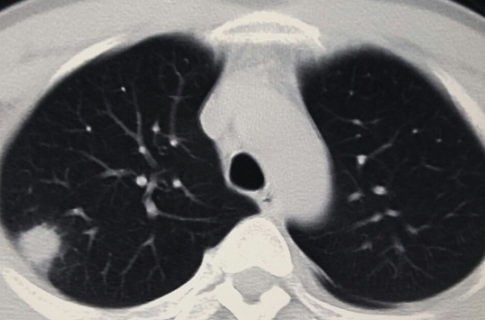

正常人群肺结节检出率因地区而异。根据目前的情况,最低可能是20%,最高可能是40%-50%,甚至70%,这可能与参与调查的正常人群有所不同。年龄不一样。 30-70岁的正常人可能会发现70%的人有肺结节,一般在20%-40%左右。肺结节发生率高,但恶性程度低。有可能90%以上的肺结节是良性结节,最终诊断为恶性肿瘤的约有5%左右。

肺结节的发病率虽然高,但主要是由非肿瘤因素引起的。由于肺癌是最常见的癌症,大家对肺癌的关注度也越来越高。肺癌的监测和筛查方法通常是胸部CT。胸部CT做的越多,肺结节的发生率和检出率就会增加。由于肺癌仅占其中的5%左右,因此肺结节大可不必过于紧张。 .必要的检查、观察和随访更为重要。做到早筛查、早发现、早治疗。大多数肺癌患者都能取得较好的治疗效果。